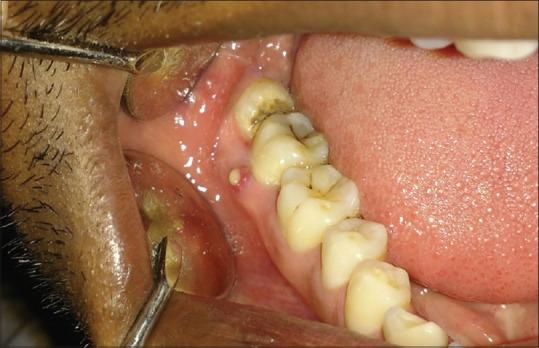

Caries in second molar is common and prophylactic removal of the impacted teeth may be considered appropriate. Caries detection and restoration can be difficult and a restored second molar can undergo recurrent caries if the third molar is not removed prophylactically. In this study, the clinical findings related to impaction and its association with angular position and depth of impacted third molar were evaluated.

A total of 200 patients were included in the study between age group 17-45 years. Majority of the Patients reported to the hospital with complaints of decayed tooth (66%) and pain (59%). The most common third molar impaction was mesioangular followed by distoangular. A statistically highly significant difference ( = 0.001) was obtained with the presence of caries in second molar adjacent to mesioangular third molar in class I and level B.